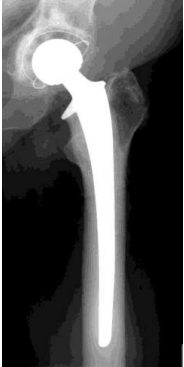

Operative Frakturbehandlung

Endoprothese

völlig zerstörtes Gelenk

nicht erhaltene Knochendurchblutung

in der Regel großes Gelenk (Oberarmkopf, Ellenbogen, Hüfte, Knie, Sprunggelenk)

evlt in Verbindung mit Knochenzement

Teil- oder Totalersatz